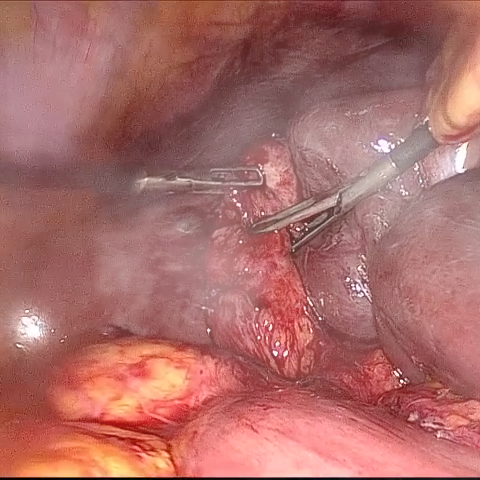

Refer to caption (a) Input Refer to caption (b) DIACMPN Refer to caption (c) Desmoke-LAP Refer to caption (d) PFAN Refer to caption (e) MITNET Refer to caption (f) Salazar Refer to caption (g) Dehamer Refer to caption (h) Ours Refer to caption (i) Target

Figure 3: Comparison of different methods on the LSD3K dataset.

IV-C2 Qualitative Analysis

Figures 3 and 2 provide a visual comparison of the desmoking results on challenging images from the test sets. The visual results corroborate our quantitative findings. DCP not only fails to remove the dense smoke but also introduces severe color distortion. CNN-based methods like FFA-Net and MSBDN successfully remove a large portion of the smoke but tend to either leave behind a thin layer of residual haze or over-smooth the image, losing critical textural details of the tissue and surgical instruments. The Transformer-based methods, DehazeFormer and PFAN, produce significantly better results by restoring more details. However, they can sometimes struggle with non-uniform smoke distribution, resulting in regions with unnatural brightness or minor artifacts.

In stark contrast, our RGA-Net generates visually superior results that are remarkably close to the ground-truth images. It effectively removes even the densest plumes of smoke while simultaneously preserving fine-grained details, such as blood vessels, tissue textures, and reflections on surgical tools. Furthermore, the color and illumination of the restored scene appear more natural and consistent, which is a direct benefit of our model’s ability to handle both local and global features through its hybrid attention and cross-gating mechanisms. This enhanced visual clarity is crucial for improving the surgeon-robot interface in real-world clinical applications.